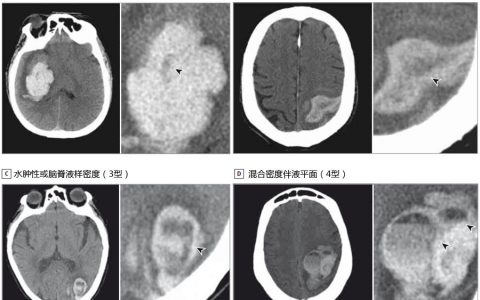

• JAMA Neurol:急性脑出血后如何预测血肿扩大?

一项回顾性研究结果显示,在急性脑出血后的第一个48小时内,血肿内出现低密度影可能预示着血肿的扩大。这一研究结果在线发表于JAMA神经病学杂志。 “这种由非对比CT扫描检测出的低密度可以预测由于持续出血导致的血…